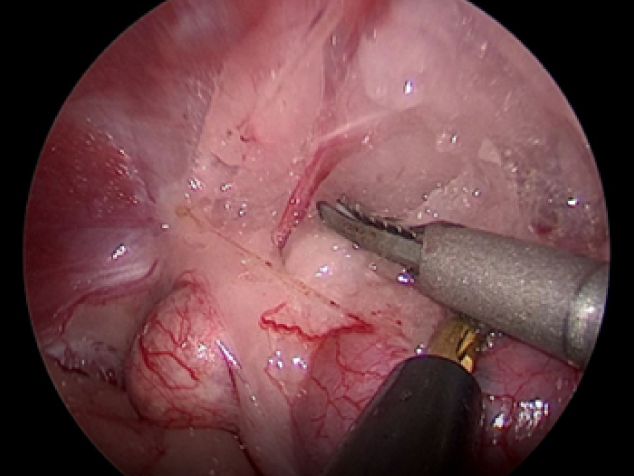

まずは腎臓、副腎と腹壁がくっついているところをはがしていきます。 脂肪の中に血管が隠れているのでそれを出血させないように丁寧にはがしていきます。 血管は電気メスや超音波メスを使って止血していきます。

実際の手術風景です。